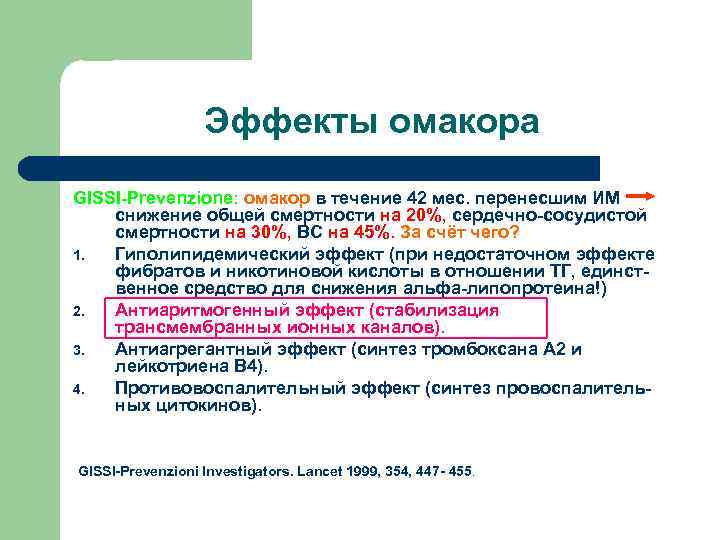

Эффекты омакора GISSI-Prevenzione: омакор в течение 42 мес. перенесшим ИМ снижение общей смертности на 20%, сердечно-сосудистой смертности на 30%, ВС на 45%. За счёт чего? 1. Гиполипидемический эффект (при недостаточном эффекте фибратов и никотиновой кислоты в отношении ТГ, единственное средство для снижения альфа-липопротеина!) 2. Антиаритмогенный эффект (стабилизация трансмембранных ионных каналов). 3. Антиагрегантный эффект (синтез тромбоксана А 2 и лейкотриена В 4). 4. Противовоспалительный эффект (синтез провоспалительных цитокинов). GISSI-Prevenzioni Investigators. Lancet 1999, 354, 447 - 455.